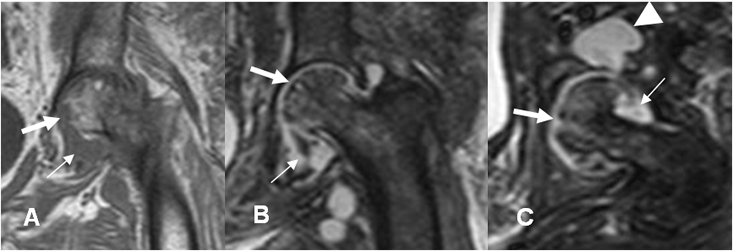

Fig 143 A. Artritis infecciosa.

A: RM coronal en T1. Destrucción de la cabeza femoral y derrame articular, por artritis infecciosa.

B: RM axial en T1 simple y C: RM axial en T1 con contraste. Proliferación sinovial, que realza con el contraste (Flechas).